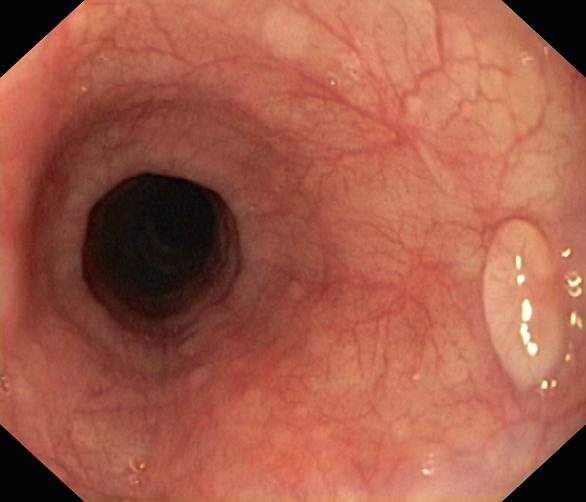

Polipy